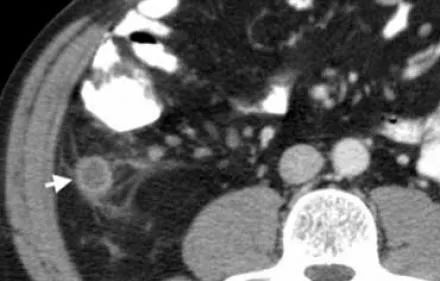

正常阑尾的最大外径为6mm,周围是均匀的非炎症脂肪,通常含有腔内气体。如下图

下图43岁男性阑尾炎。增强CT显示一个充满液体的扩张阑尾(箭头)与阑尾周围脂肪缠绕。